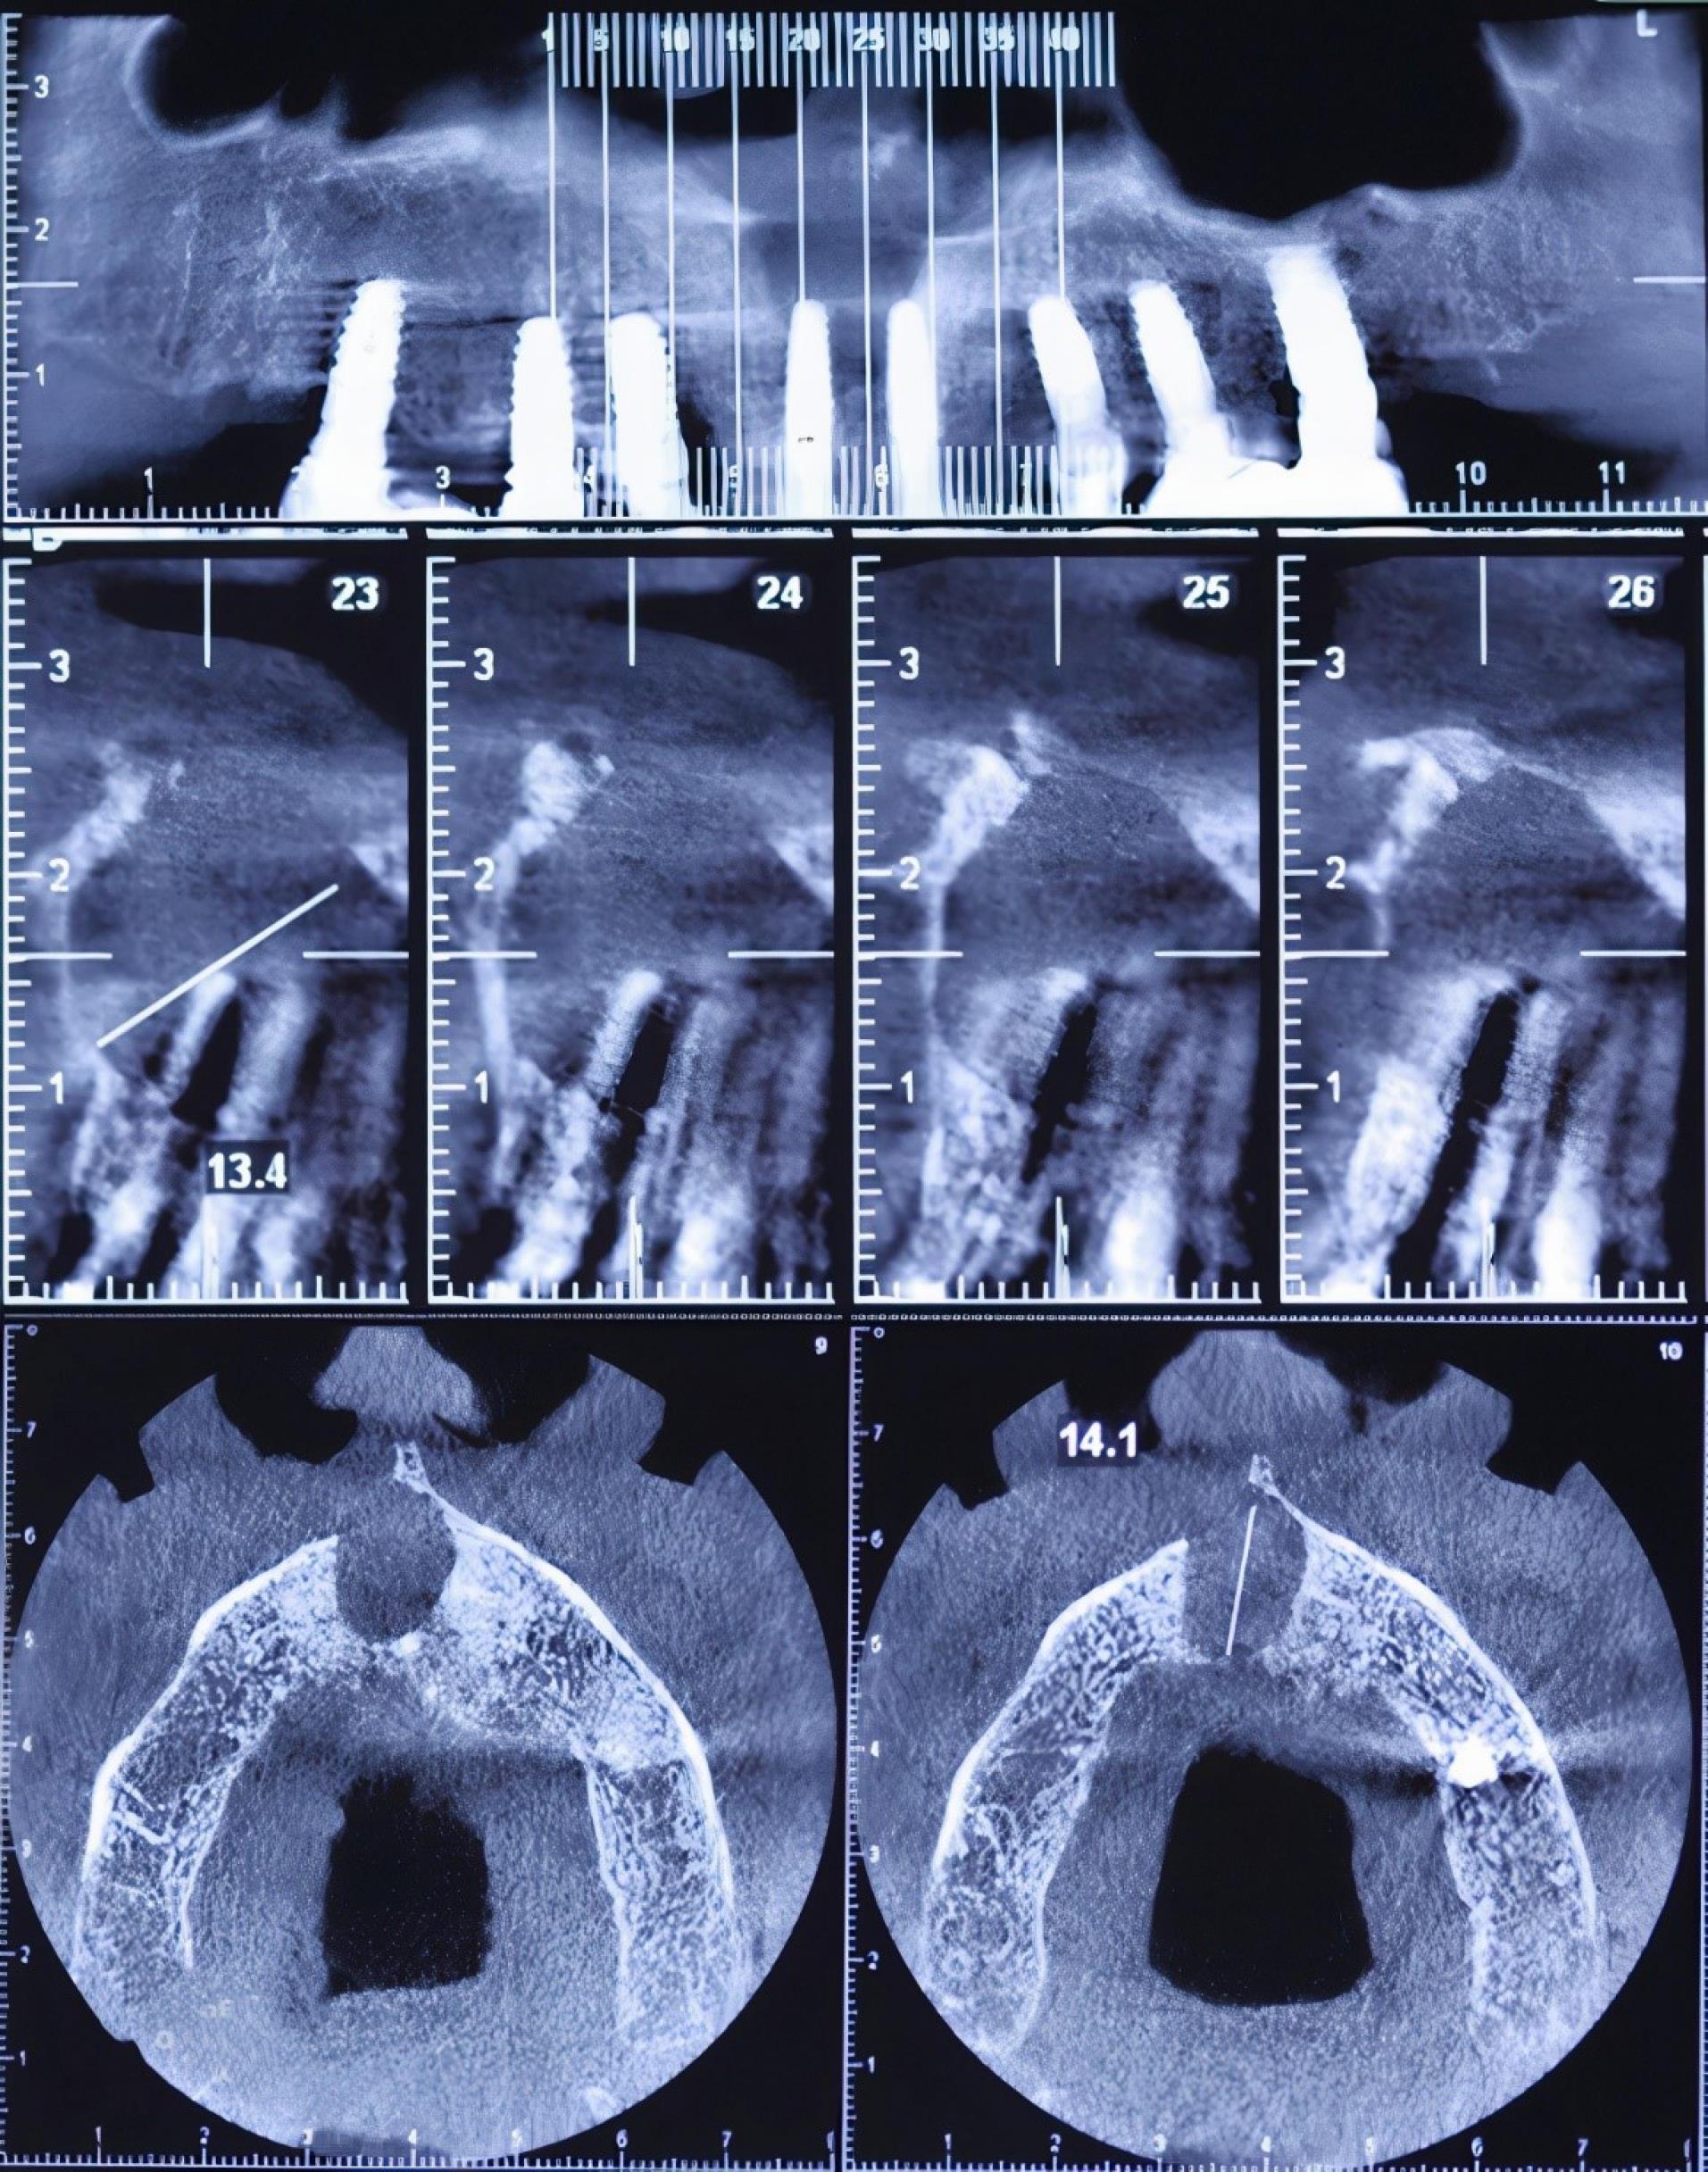

A full radiographic examination was requested. Following radiographic evaluation of panoramic radiograph and sections of cone-beam computed tomography (CBCT), an oval-shaped, unilocular radiolucency with a well-defined boundary was observed that not only surrounded the apex of the right central implant but also disturbed the nasopalatine canal and nasal floor (Figures 1 and 2).

Figure 2.

Cone-beam computed tomography (CBCT) imaging of the maxilla. Sections #23 and #24 show the disturbance of the nasopalatine canal and the nasal floor

In this case report, the cyst was fully removed, and since no problem was observed with the implant, no additional treatment was undertaken. Surgical planning should be based on the findings of CBCT imaging because the measurement of the nasopalatine canal, its location, and the defect morphology are better observed compared to conventional radiographs.